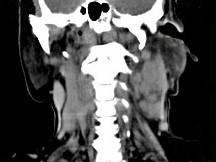

问题 女,69岁,低热、乏力三月余,消瘦,食欲不佳,PE:腹股沟触及多个肿大的淋巴结,质较硬,尚可移动,CT如图所示,最可能诊断为()

选项 A.淋巴瘤 B.颈淋巴结结核 C.颈淋巴结结核 D.结节病 E.淋巴结炎

答案 A